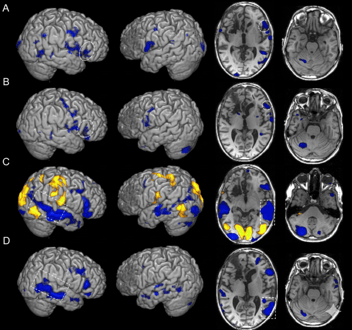

Dr. Allen and Dr. Fong began research together over a decade ago in search of a way to improve and standardize the functional MRI. Their research efforts in imaging provided a way to see changes in the brain after a concussion -- a novel discovery. This discovery led them to focus their research efforts on concussion, post-concussion syndrome or symptoms, and its treatment. Without this discovery, we would not be where we are today.